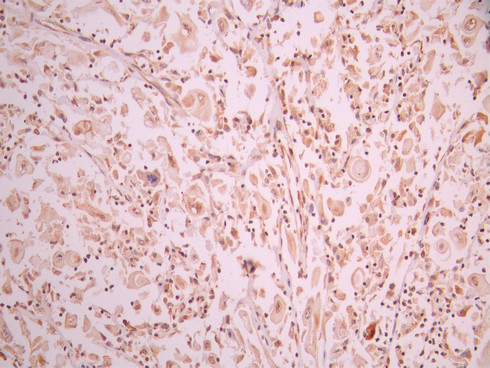

IHC image of CSB-RA775975A0HU diluted at 1:100 and staining in paraffin-embedded human cervical cancer performed on a Leica BondTM system. After dewaxing and hydration, antigen retrieval was mediated by high pressure in a citrate buffer (pH 6.0). Section was blocked with 10% normal goat serum 30min at RT. Then primary antibody (1% BSA) was incubated at 4°C overnight. The primary is detected by a Goat anti-rabbit polymer IgG labeled by HRP and visualized using 0.05% DAB.